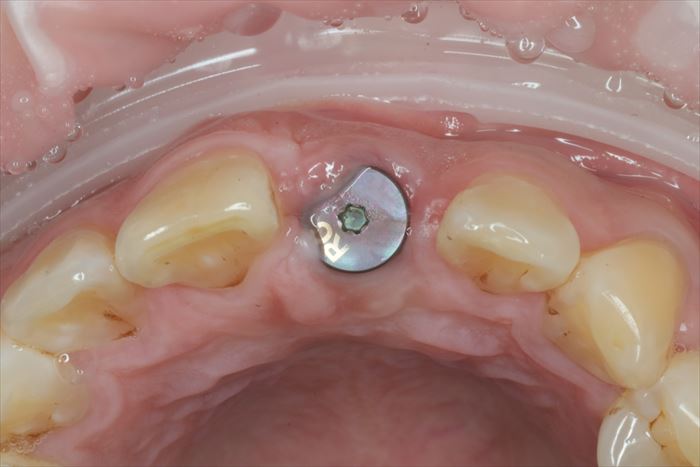

チタンベースにジルコニアを接着したジルコニアカスタムアバットメントを締結します。

ジルコニアカスタムアバットメントを締結しました。

アバットメントによって歯肉の形をマネージメントします。